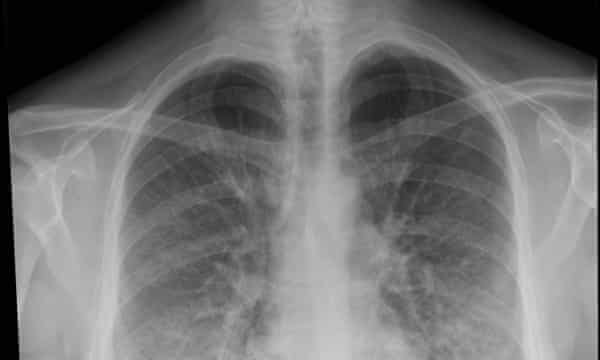

Pneumonia is spread through coughs sneezes and touch or by breathing germy air. Pneumonia is detected through chest X-rays physical examination and other tests such as arterial blood gas test and is ideally treated with antibiotics. Walking pneumonia refers to mild cases of bacterial pneumonia.

Pneumonia is a disease of the lungs that often results from a lung infection. Viral pneumonia accounts for about a third of cases. Certain common symptoms of Pneumonia are fever chills cough breathlessness palpitations fatigue weakness chest ache nausea vomiting and diarrhea.